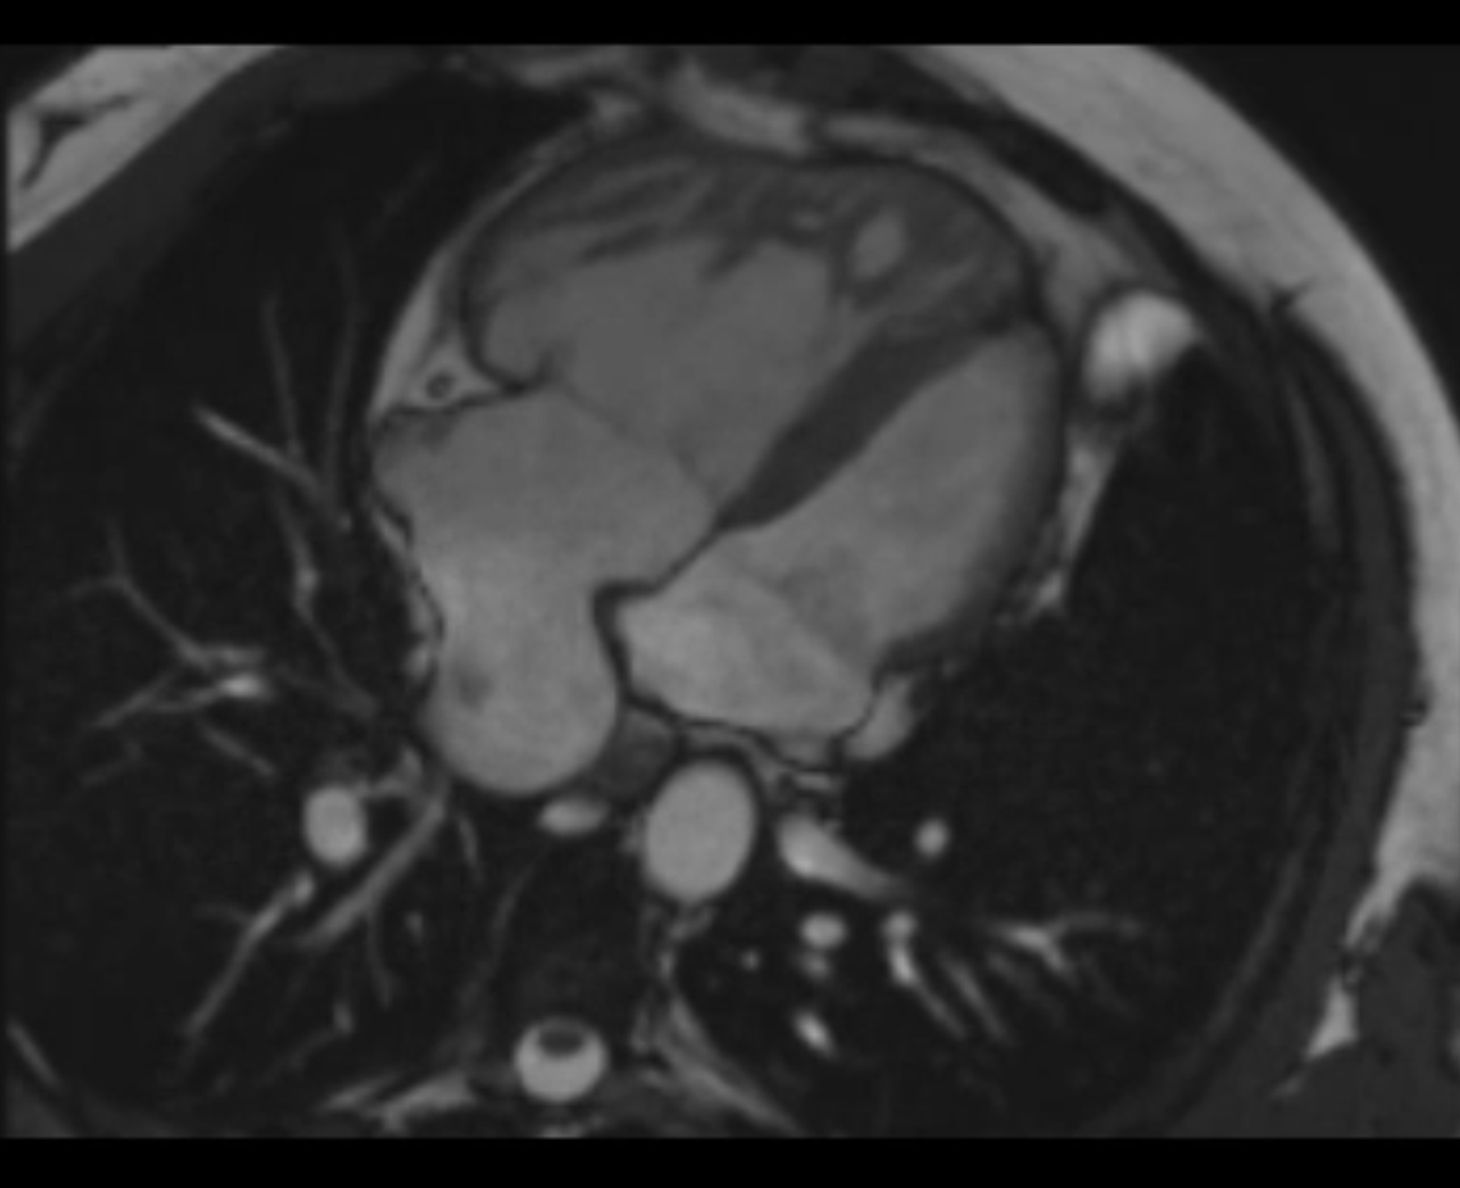

Die kardiale MRT ermöglicht in allen Altersstufen eine hervorragende Darstellung des Herzens und der Gefäße. Sowohl Struktur als auch Funktion lassen sich mithilfe dieser Untersuchungsmethode umfassend beurteilen. So können Fehlbildungen des Herzens und der Gefäße auch bei Säuglingen und Kleinkindern (in Narkose) sehr genau dargestellt werden. Komplexe Herzfehler können den Chirurgen mittels moderner Rekonstruktionstechniken als virtuelles oder reales 3D-Modell zur Verfügung gestellt werden. Zur Anwendung kommen modernste MRT-Scanner (1,5T u. 3T) der Fa. Siemens Healthineers.

Die Kombination der unterschiedlichen MR-Verfahren ermöglicht eine umfassende anatomische Darstellung der Struktur des Herzens und der großen Gefäße: